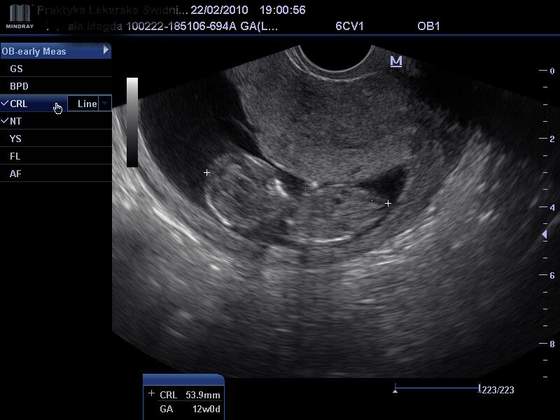

Dziewuszki wczoraj miałam wizyte u gina. Dzidzia dobrze sie rozwija, ma całe 53,9 mm

A tu Wam wklejam zdjątko- mało na nim widać, ale chce się pochwalić MOJĄ dzidzią